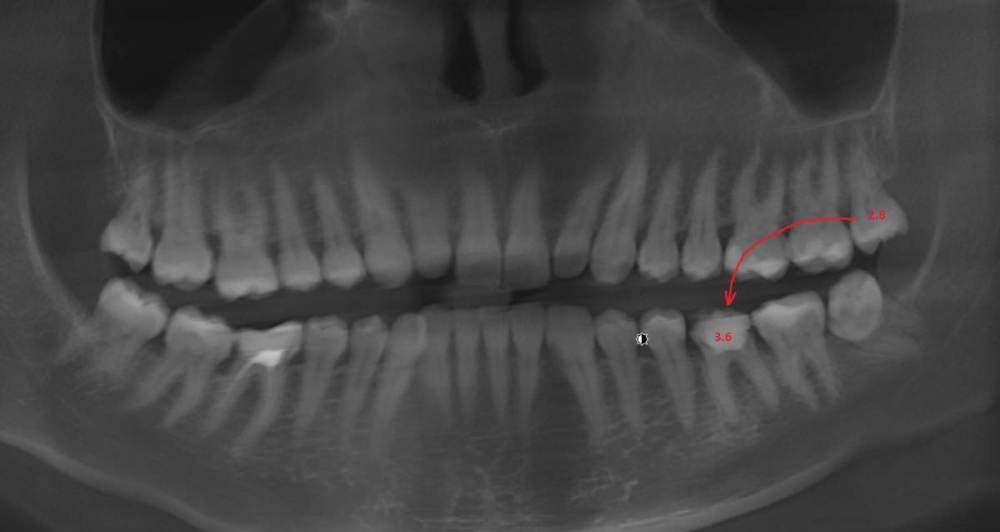

Dr.Deletle Опубликовано 22 июля, 2023 Поделиться Опубликовано 22 июля, 2023 (изменено) Этот кейс интересен тем, что у пересаживаемого 2.8 полностью сформированы корни. Пациент Н., 35лет, зуб 3.6 подлежит удалению по терапевтическим показаниям. Донором был выбран зуб 2.8. Фото №1, 2 - ситуация ДО на фото и срезе КЛКТ Фото №3 - планирование на реконструкции ОПТГ из КЛКТ Фото №4 - шаблон зуба 2.8 Фото №5, 6 - операция, удален 3.6, припасован шаблон, пересажен 2.8 (фиксирован швами и шиной к 3.7) Фото №7 - КТ сразу после пересадки Фото №8, 9 - депульпирование пересаженного 2.8 через 2 недели Фото №10 - снятие шины через 2нед после пересадки Фото № 11, 12, 13 - состояние в полости рта и на срезе КТ через год после пересадки, видно сформированное периодонтальное пространство, здоровая костная ткань, жалоб у пациента нет, полноценно жует как обычным зубом Изменено 22 июля, 2023 пользователем Dr.Deletle 4 3 Ссылка на комментарий